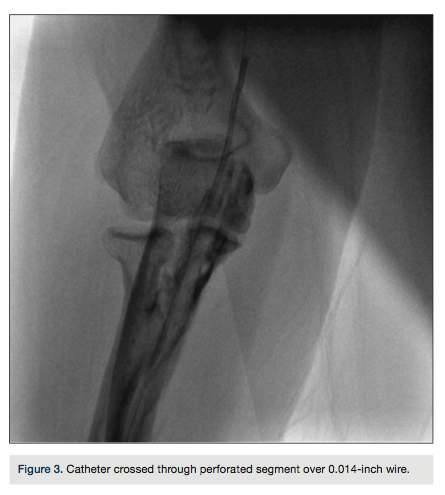

A 0.014-inch percutaneous transluminal coronary angioplasty wire was tactfully and carefully advanced through the area of perforation under fluoroscopic guidance (Figure 2). A diagnostic

catheter was inserted up to the proximal axillary artery over the wire (Figure 3). The wire was exchanged for a 0.035-inch, 260-cm long wire through the catheter. During left heart catheterization, this wire maintained position in the ascending aorta to exchange the catheters. The patient received 50 units/kg of unfractionated heparin during the procedure. Diagnostic coronary angiography demonstrated normal coronary arteries with mild luminal irregularities. The procedure was completed through the same RA access obtained at the beginning of the procedure. At the end of the left heart catheterization, the catheter was pulled